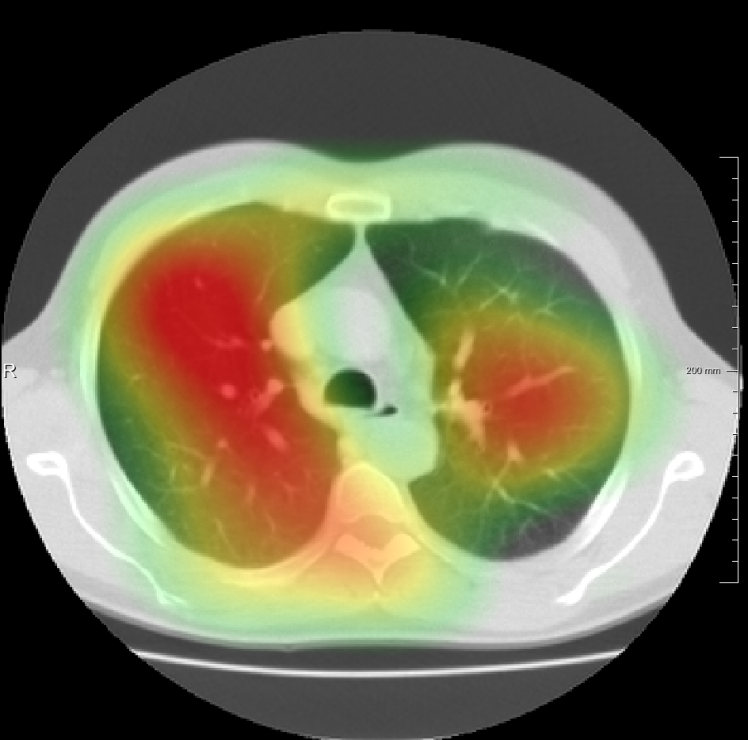

In total we generate 14 basis types of artificial DVFs: 5 single frequency, 4 mixed frequency, 4 respiratory motion and 1 identity. The precise settings of the parameters are available in Table I and examples are given in Fig. 4. The histograms of the Jacobians are also available in this figure. When the spatial frequency is increased, the Jacobian histograms will spread more, which shows that local relative volume changes are increased. The value of , the maximum artificial displacement along each axis, is chosen as 20, 15 and 7 for RegNet4, RegNet2 and RegNet1, respectively.

For the DIR-Lab-4DCT database, a comparison between RegNet and affine, B-spline (three resolutions), an advanced conventional registration method using sliding motion (Berendsen et al., 2014) and three other CNN-based methods (Eppenhof and Pluim, 2018; de Vos et al., 2019; Sentker et al., 2018) is available in Table IV. It can be seen that training with “S+M” improved performance slightly with respect to just “S”. Adding the respiratory motion category improved performance substantially, as these are inhale-exhale pairs; this is predominantly caused by the patients where the TRE after affine registration was still quite large. An example visualization is also available in Fig. 5(f), showing that adding the respiratory motion category can align images better in the diaphragm region. The advanced conventional registration method that leverages sliding motion (Berendsen et al., 2014) is still better than RegNet. Note that RegNet was not trained on the DIR-Lab-4DCT data, similar to Eppenhof and Pluim (2018); Sentker et al. (2018). However, de Vos et al. (2019) and Eppenhof and Pluim (2018)-DIR methods were trained on the same database but using cross-validation to report the results. Also note that the results reported in Sentker et al. (2018) are averaged over all phases of DIR-Lab-4DCT (T00 to T10), while the results of other CNN methods (including RegNet) are reported between the maximum inhale and maximum exhale phase (T00 and T50). These reported results are therefore likely somewhat better than the results for T00 and T50 only.